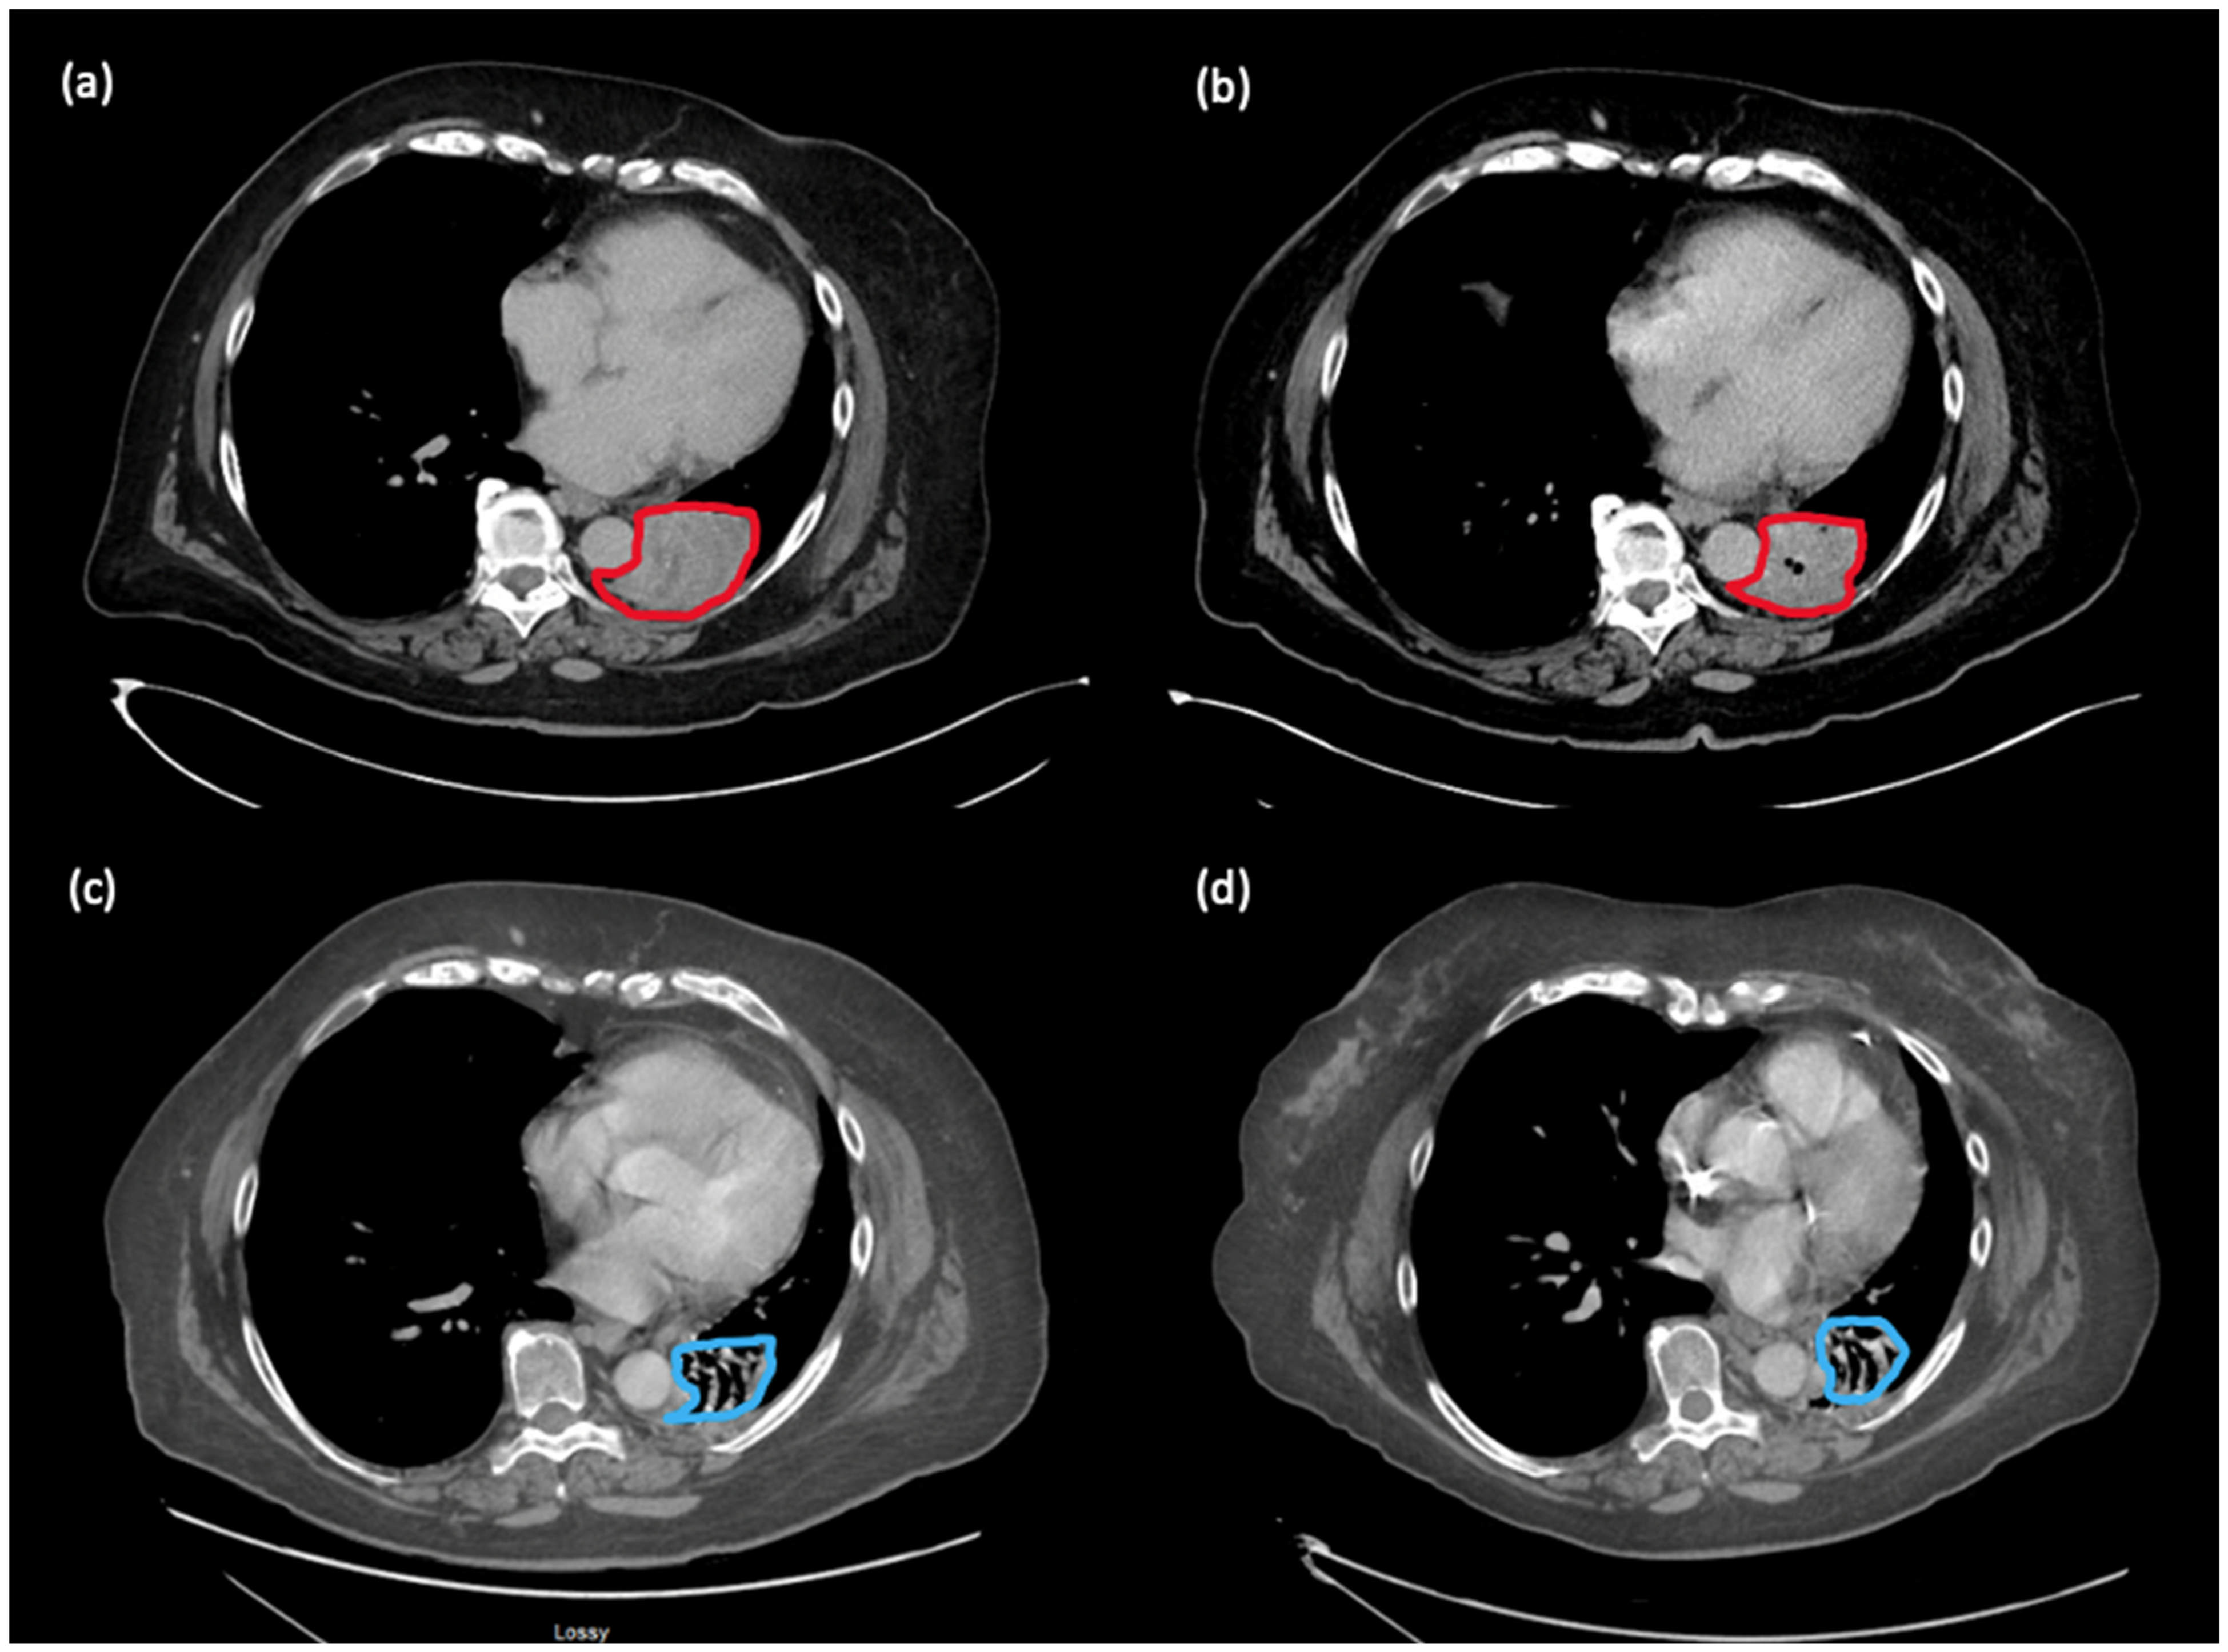

Figure 2. Evolution of perihilar metastasis in patient 1. Outlined in red is tumour; outlined in blue is residual atelectasis/fibrosis as interpreted by radiology. (a) July 2021: progression of perihilar mass after 10 cycles of maintenance nivolumab (prior to addition of CC); (b) December 2021: improvement in the perihilar mass, shrinking from 6.5 × 4.8 cm to 5.4 × 4.5 cm, after 5 months of treatment with nivolumab and CC; (c) November 2022: near complete response on nivolumab and CC; (d) February 2023: ongoing near complete response on nivolumab and CC.

In July 2021, after 10 cycles of maintenance nivolumab, there was disease progression in the perihilar mass, increasing from 2.8 × 2.7 cm to 6.5 × 4.8 cm. Treatment options were limited at this stage, and we and the patient had an interest to explore options other than chemotherapy. We considered microbiome modulation in this patient, as she had an extensive antibiotic history throughout her multiple lines of immunotherapy, which may have caused a highly altered gut microbiome. She had received cefadroxil for right calf cellulitis in 2015, levofloxacin in 2016, moxifloxacin in 2017 and amoxicillin/clavulanic acid in 2018 for suspected pneumonias, and levofloxacin in 2019 for bronchitis (see Figure 1 for timing of antibiotics in relation to immunotherapy). Work from our group and other institutions demonstrated that antibiotic use can lead to changes in the gut microbiome associated with worse survival outcomes in patients treated with immunotherapy [7,8,9]. Additionally, our basic science collaborators have used new murine models to show that CC, through its active component castalagin, can modulate the gut microbiota to re-sensitize tumours to ICIs in ICI-refractory mice with solid tumours [6]. Thus, we proposed to the patient to continue nivolumab monotherapy with the addition of 1000 mg of CC ingested orally once daily. This dose was chosen based on the Health Canada-recommended safe dosing range for CC when taken as a natural health supplement, which is 500–1500 mg per day [10]. The patient provided informed consent and proceeded with nivolumab rechallenge with CC. Subsequently, the hemoptysis improved. Scans 5 months later showed improvement in the perihilar mass, shrinking from 6.5 × 4.8 cm to 5.4 × 4.5 cm. Scans conducted in November 2022 demonstrated a near complete response (disappearance of perihilar mass, two 5 mm lung nodules). Scans in February 2023 demonstrated the same ongoing deep response with 18 months of treatment on this regimen (see Figure 2). Clinically, the patient remains asymptomatic from melanoma. She has not had any hemoptysis, which was associated with previous progression of her cancer. Since starting CC, she has not had other irAEs aside from grade 1 non-bloody diarrhea, which has responded well to loperamide.